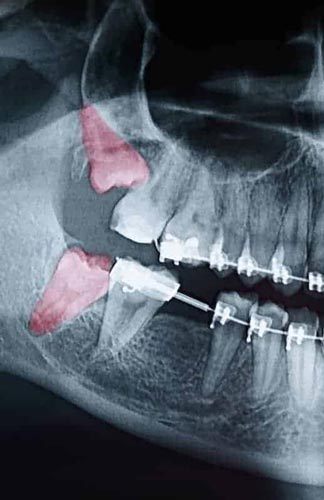

Most people’s mouths only have enough room for 28 teeth. When your wisdom teeth start to come in, that’s four additional teeth trying to cram their way in. In the majority of situations, this creates a litany of problems, including crowding, soreness, risk of infection, and the need for extraction. Since your wisdom teeth are the last teeth to erupt through your gums, they come to the party a little late. All your other teeth have settled into their places. With x-rays and inspections, we can determine if your wisdom teeth are impacted and need to be removed. Since wisdom teeth rarely come in straight and even with the rest of your smile, we have years of experience analyzing them and extracting them at the Center for Oral & Facial Surgery. Wisdom teeth can also come in sideways, causing even more issues for you if we don’t act. If you or your child is approaching the age of 18, it’s crucial to bring them in for an examination for their wisdom teeth. Call us today to schedule your appointment for a wisdom teeth analysis or extraction in the San Diego area.

Though some patients may not require the removal of their wisdom teeth, most often, it’s needed to protect your overall oral health. Wisdom teeth can begin to grow in sideways, only partially erupt, or even get stuck beneath the gum and bone. Known as impacted teeth, those that get stuck may resort to shifting position as they try to find a pathway for eruption. When wisdom teeth don’t erupt through the gumline properly, they can create severe problems for the patient, including:

To evaluate the state of your wisdom teeth, we’ll first do a thorough examination and take x-rays of your mouth. This will help us determine if your wisdom teeth pose a current or future threat to your oral health. Early detection of issues results in better outcomes for our patients, so we recommend the first evaluation be completed in a patient’s mid-teenage years.